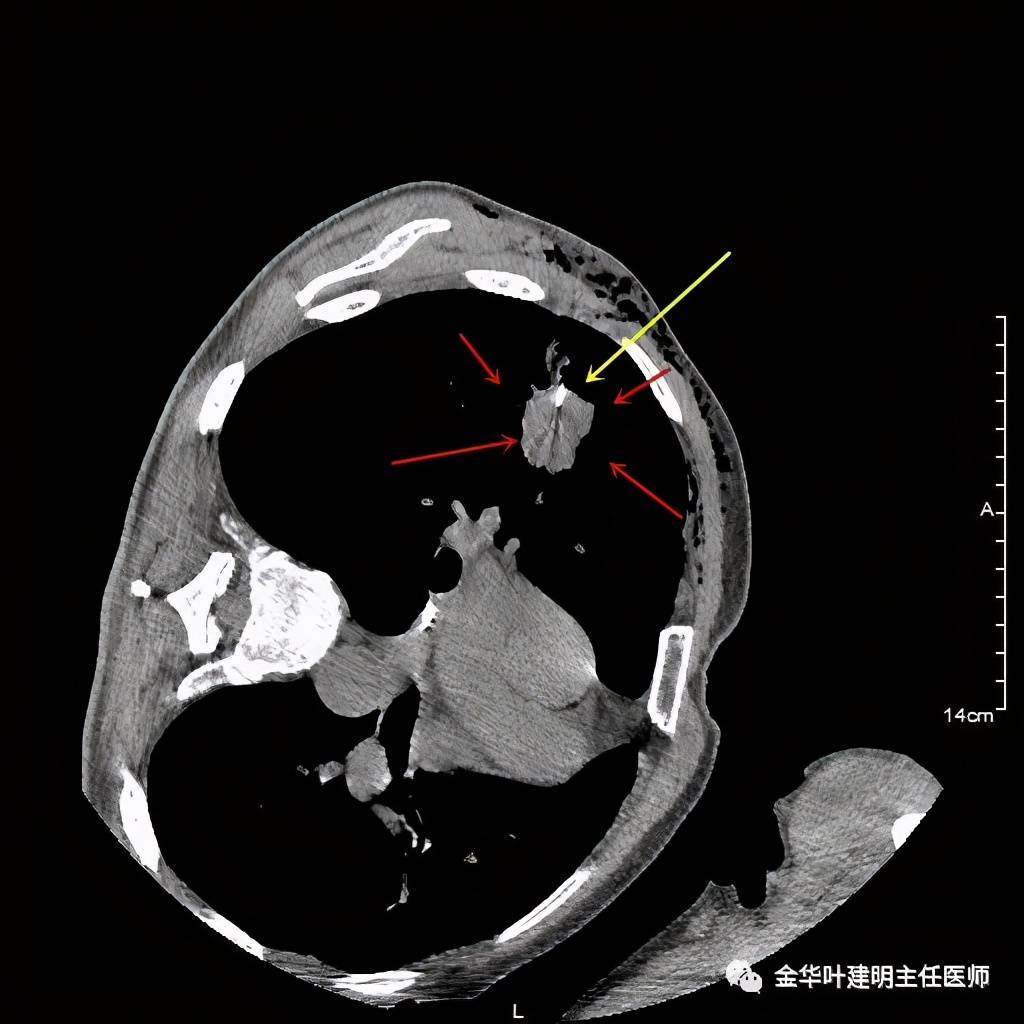

上图黄色箭头示穿刺针进入的地方,位置还是非常好的,应该容易穿到有价值的病变组织。但穿刺结果未见肿瘤:

病理不支持!怎么办?是抗炎治疗了先出院随访,还是仍手术?如果穿刺阴性仍予以手术,感觉穿刺失去了价值;如果不手术放回去,这样影像表现的病灶能放心认为是慢性炎吗?患者家属找到我,问我的意见,应该如何。我们先再来看看病灶的影像细节:

上图是穿刺时的某个层面,病灶的细毛刺征比较明显(蓝色箭头),病灶的边缘是不平的,而且有细短的毛刺样突向周围肺组织,这可是恶性的特征

桔色箭头示病灶周围血管征明显,有较粗的血管进入病灶,较细的也有

上图箭头示强化的血管与病灶关系密切,而且有被病灶侵犯影响的感觉,部分界限是不清楚的

上图紫色箭头示明显的叶间胸膜牵拉,红色箭头示病灶,中间还有空腔,边缘有细毛刺,感觉上病灶就是有收缩力而僵硬的

上图示病灶内部有条索状的强化影,考虑是病灶内的新生血管可能性大

上图也见细毛刺,但不是特别广的范围,有的边缘还是相对比较光滑了点

上图示病灶强化不等,表现不平,中间有空洞,空洞旁边有偏低密度区(坏死?)

上图示病灶膨胀分叶,表面不平,像个土豆

上图示病灶密度不均,有偏低密度的区域

上图黄色箭头示空洞形成,病灶表面不平